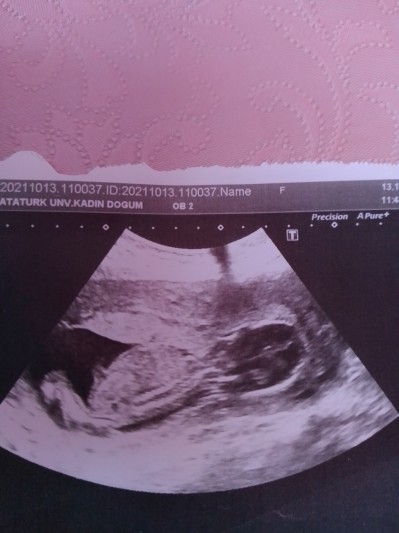

Kızlar 17 haftalık hamileyim doktor cinsiyetini göstermiyor yan durmuş dedi. Bir cinsiyet tahmini yapabilir misiniz çok merak ediyorum. Doktorun görmediğini biz nasıl görelim diyenler cevap vermesin lütfen. İnsan ister istemez merak ediyor.

Gebelik haftası 17

Erkek canım erkek çok belli :) benim de aynen birberir böyle bı pozu var erkek benimde . Bide çıkıntı görünüyor zaten

O çıkıntı göbek kordonu. Pipi olsa doktor görüp erkek derdi.

Çıkıntı Kordon yanlız :) ama bende erkek diyorum hierime dayanarak

Bencede kız cnm erkek daha toplu durur ultrasonda :)

Kız bu ya :)) içimden öyle geçti çıkıntı var evet ama o şeyi olsa doktor da görüp direkt erkek derdi zaten

Bebeğimin cinsiyetini öğrendim kız ☺️

Herkesin pipi sandığı o şey pipi değil göbek kordon girişi. Pipisinin orda ne işi var bacaklara bakın uzatmış onun arasında olur pipisi bu bebek kız olabilir bnce.

Kız bebek canım hem erkek olsa 17.ci haftaya kalmadan belli ederdi kızlar geç belli olur derler sağlıklı olsunda :)

Canım bende 16 hafta 2 günlük hamileyim ultrason resmi aynen böyle uzun duruyordu fasulye gibi ve bebegin tipi bile benim bebisle çok benziyor iki gün önce gittim erkek dedi bence senin ki de erkek :)